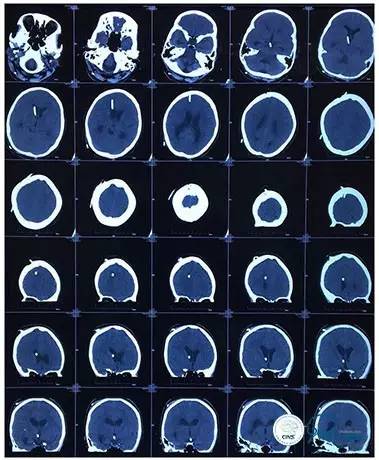

2016-06-03 CT

2017-06-07 CT

术后头颅CT